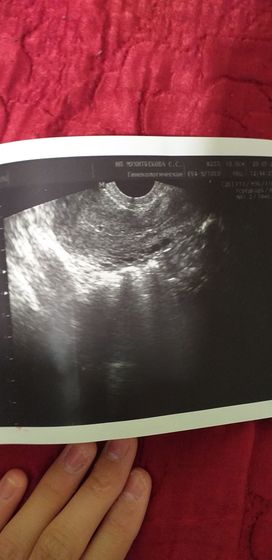

Всем доброго времени суток! мне 23 года по УЗИ сказали что возможная внематочная беременность, только как может быть такое внематочная в полости матки? переживаю первая беременность подскажите

Здесь нашему яичку было 2 недели и 6 дней

мне сказала гениколог что УЗИ с 4 недели самого плода показывает наличие беременности, скорее всего малыш совсем мал

у меня тогда УЗИ тоже не показала беременность, делала трансвагинальное ))

я такое же делала показало очень маленькое

У вас в матке плодное яйцо, я его виду, сходите в другое место переделайте узи

У вас как раз в матке чисто. Нет ничего

сверху в левом углу есть маленький круглешочек

Я такое видела, когда не была беременна, это же может быть хоть что… Если бы тут было плодное яичко, зачем бы поставили под подозрение внематочную? Сколько срок должен быть?

ну она сказала или маленький срок, или внематочная как будто не знает. ну может недели 2-3 поэтому не показало